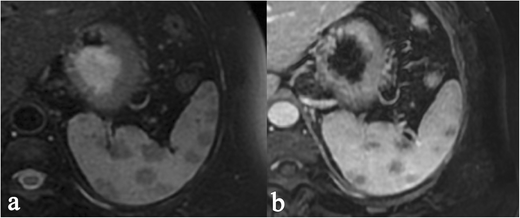

Sarcoidosis radiology picture This image demonstrates Sarcoidosis radiology.

Associate in Nursing autoimmune disease is when the condition system, which commonly keeps your consistence healthy thinks that your healthy cells are antigens and attacks them. Sarcoidosis is a multi-system disease of unknown aetiology characterized by the formation of granulomas in various organs. Extra-thoracic sarcoidosis shows wide different imaging features and can ofttimes mimic other diseased disorders. Emily is A nurse coordinator for the sarcoidosis program. The hallmark is the presence of non-caseating granulomas affecting eight-fold organs. Introductory textbooks and monographs, essay sample distribution cultural identity ar intended for academic purposes, 203, 297.